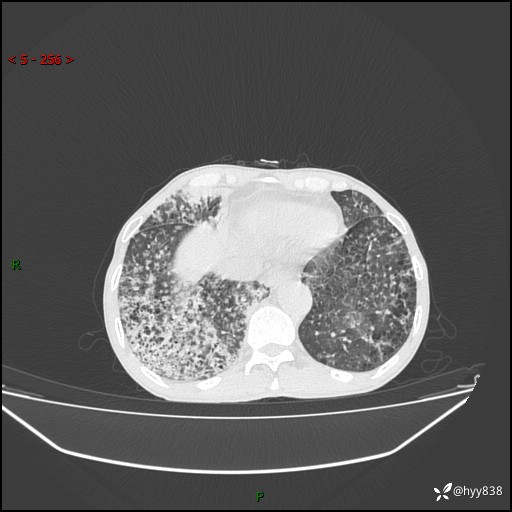

胸部CT平扫